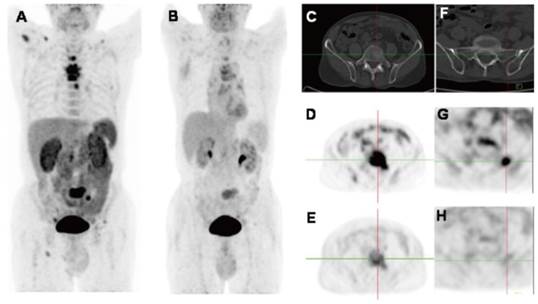

Figure 3

(A) [18F]Galacto-RGD PET images in a patient with invasive ductal breast cancer of left breast, axillary lymph-node metastases on the left side, an osseous metastasis to the sternum, and a pulmonary metastasis on the right side. Maximum-intensity projection of [18F]Galacto-RGD PET and planar images show primary tumor, lymph-node (LN) metastases, and osseous metastasis with good tumor/background contrast. (B) [18F]Fluciclatide PET/CT images in a patient with malignant melanoma. Axial, sagittal and coronal images show focal radiotracer uptake within a left supraclavicular mass. Reproduced with permission from references [50][52].

One of the applications of RGD PET in the clinic is for tumor detection and staging, as integrin αvβ3 is a well-established biomarker of neoangiogenesis. A wide variety of tumor types were evaluated in clinical studies, e.g. glioblastoma multiforme (GBM), squamous cell carcinoma of the head and neck (SCCHN), non-small cell lung cancer (NSCLC), breast cancer, melanoma, sarcoma, renal cancer, rectal cancer etc., with decent tumor/background contrast (Table 3). For [18F]Galacto-RGD, tracer accumulation in tumor lesions showed great heterogeneity, with mean SUVs ranged between the background level to a maximum of 10 [16] (Figure 3A). Summarized from all the studies reported, the sensitivity of [18F]Galacto-RGD PET for all lesions falls in the range of 59-92%. To be specific, the sensitivity for primary lesions range between 83% and 100%, however, the sensitivity for metastatic lymph nodes (LNs) was only 33-54% and was 46-78% for distant metastases [16, 33, 39, 48-51]. Another 18F-labled RGD compound [18F]Fluciclatide, like [18F]Galacto-RGD, showed heterogeneous tumor uptake with SUVs from 1.4 to 40 (Figure 3B). The sensitivity for all lesions ranged from 88-94% and was 71-88% for distant metastases [37, 52]. These data demonstrated that the monomeric peptide tracer [18F]Galacto-RGD or [18F]Fluciclatide had only moderate sensitivity for metastatic lymph nodes and distant metastases, insufficient for tumor staging.